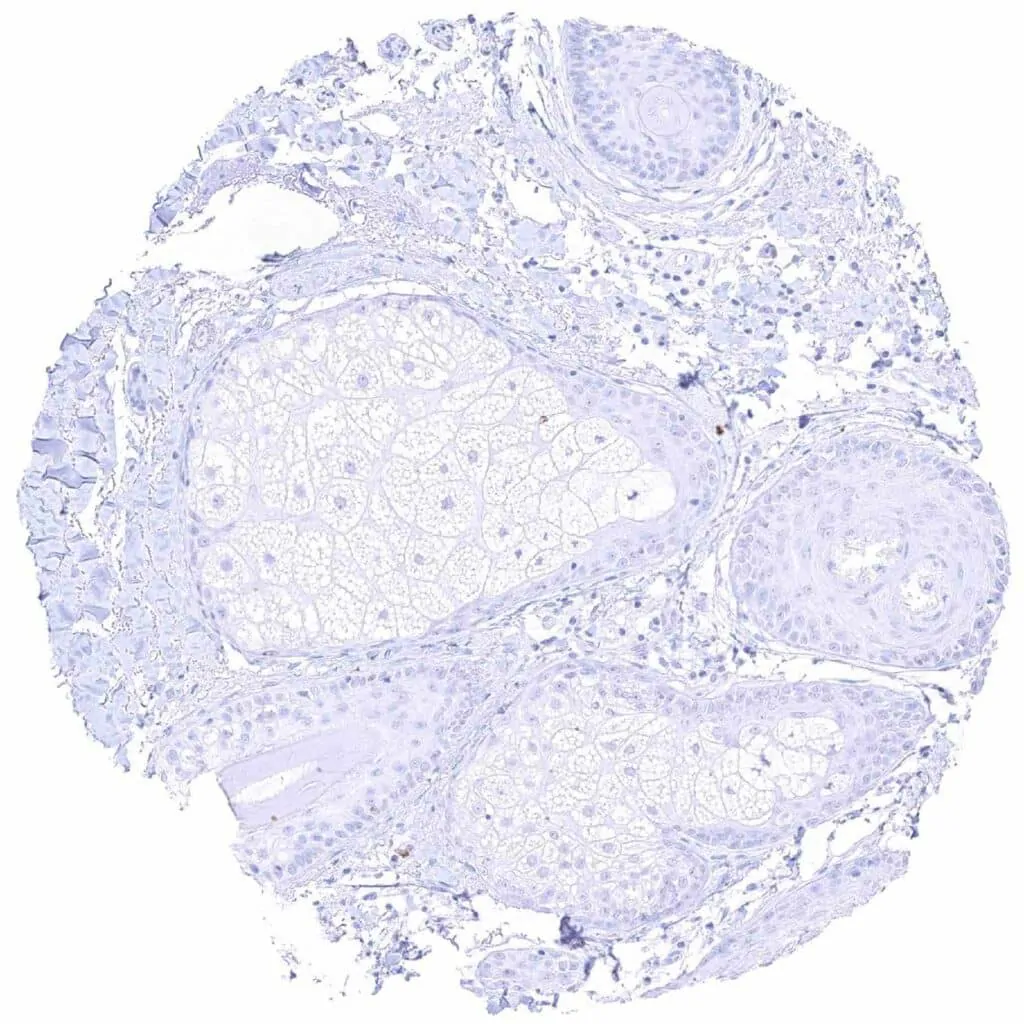

Testis